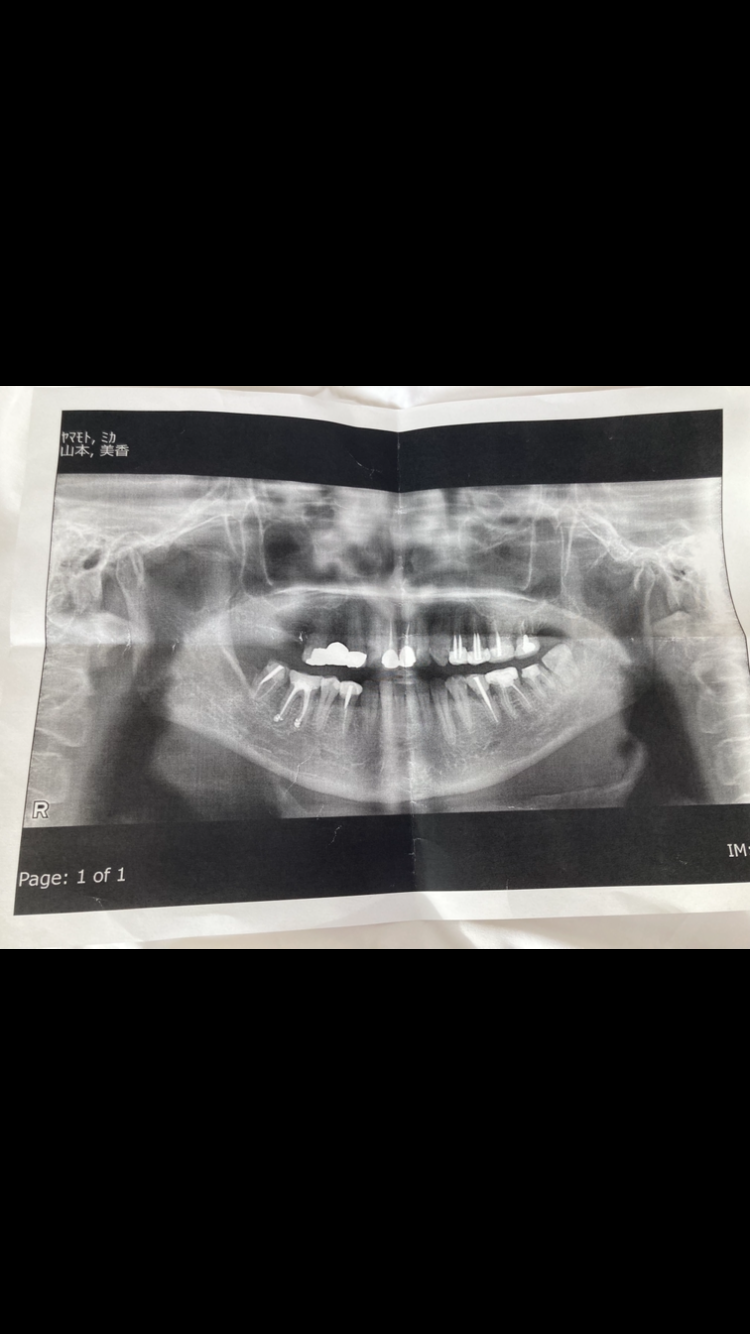

レントゲンですごく大きな薬が詰めてあるのがわかりました。

添付写真の向かって左下の左から2番目です。

レントゲンを見ても下顎管との距離は離れているようですし、直接神経を損傷しているということはなさそうに見えます。

ただ根管治療で痛みがあったという事やその後の経過によっては、骨の中で再度や浸出液が溜まり、圧力が高まり、その圧力によって下顎管の中の下歯槽神経が圧迫されて痺れが出るというようなことは考えられます。